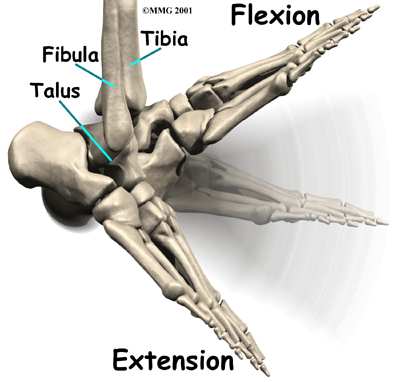

The talus moves mainly in one direction. It works like a hinge to allow your foot to move up and down.